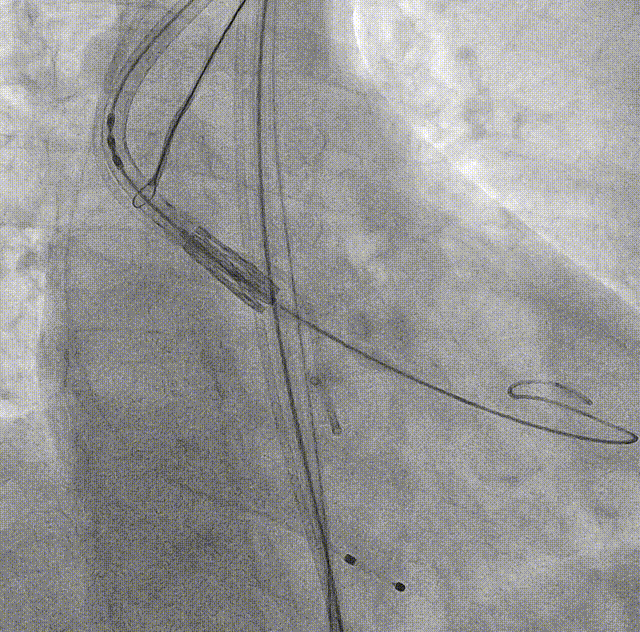

SENTINEL抗栓塞脑保护装置

良好的调弯性能,轻轻拉动圈套器即可轻松过弓

横位心68°升主扩张且右无局部粘连,圈套器辅助跨瓣